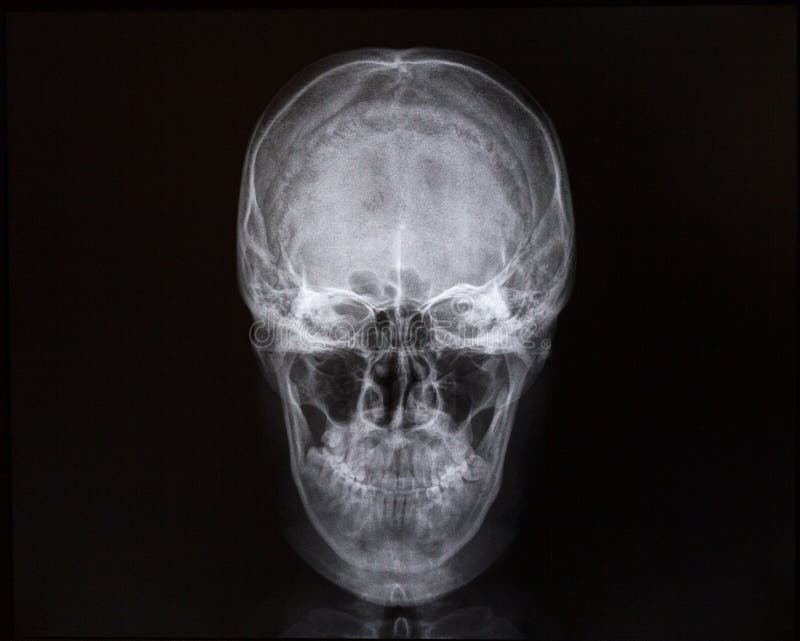

Анатомия детского черепа: Рентгеновские снимки и описание